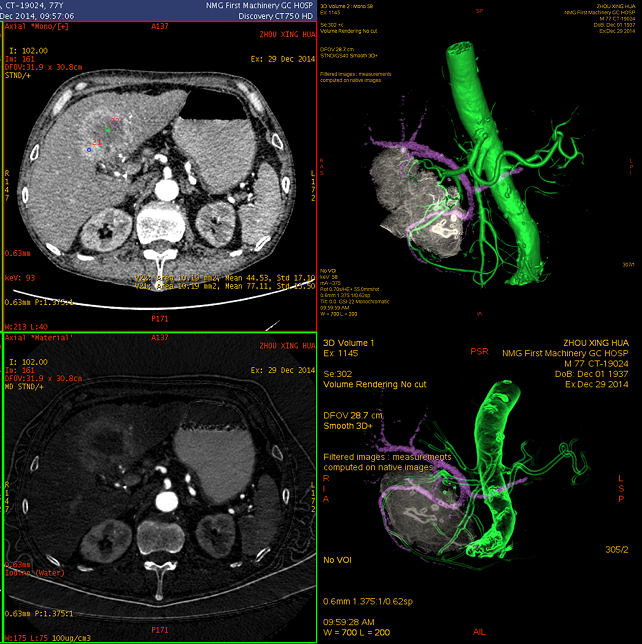

三维融合图像清晰显示病灶轮廓:肝动静脉呈“抱球征”,提示横断位图像所见的肝左叶区域的病灶并非肝实质内,而为受压及部分容积效应所致

胃恶性淋巴瘤 起自粘膜层,并向粘膜下层和肌层呈浸润性生长。病变可单发或多发,可局部侵犯,也可侵及全胃 临床上,该病最常需与浸润性胃癌鉴别 常规CT扫描可就病变的大小,范围,与邻近器官组织的关系作出判断,但往往缺乏有确诊价值的表现,尤其对生长巨大的病灶,其起源和与邻近结构的关系很难作出准确分析,无法明确地鉴别浸润性胃癌,仅能结合消化道造影对该病作出估计性的诊断,该病实为常规CT诊断难点之一 能谱CT扫描GSI能谱曲线分析及基物质图像分析可对病灶的起源,与向外生长部分同源性的判定,强化程度,相关淋巴结是否同源受侵等做出较准确判断,有助提高该病CT诊断准确率。如本例,通过同源性分析,明确排除了肝脏原发病灶,明确了胃及十二指肠区巨大病灶均起源于胃,通过碘基图像,发现强化程度不及正常肝脏及胃壁,通过多期相GSI图像分析,明确了对比剂通过未受明显影响,胃尚有蠕动;综合上述征象,可比较有把握地作出胃恶性淋巴瘤的诊断。